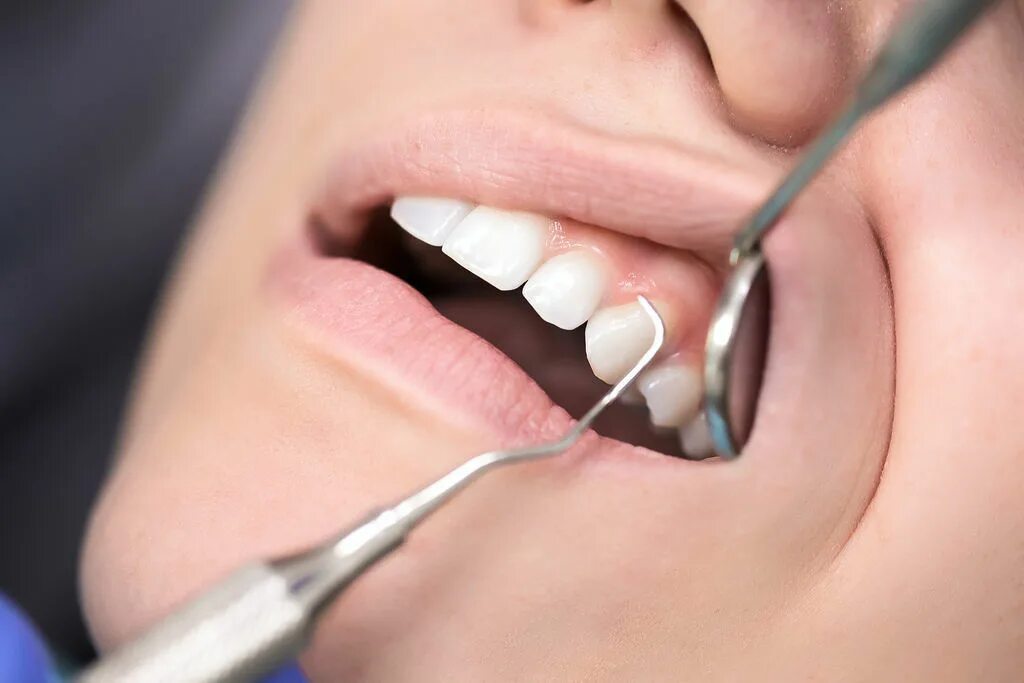

Зубной карман